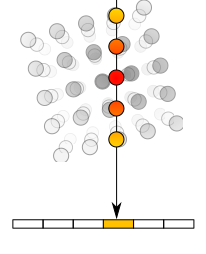

Originally the algorithm parsed the data as if the slices were independent, while in fact they have a strong 3D coherence. Also, the algorithm was pretrained with Imagenet, and it uses 3 channel images for training - RGB (Red, Green, Blue). Hence, as shown in Figure 3.6, the three channels can be fed simultaneously three slices of the volume analyzed, one at each RGB channel (2.5D approach), while during testing only the central output slice is kept. Figure 3.6 refers to the liver segmentation, but the approach is the same for the lesion segmentation network.